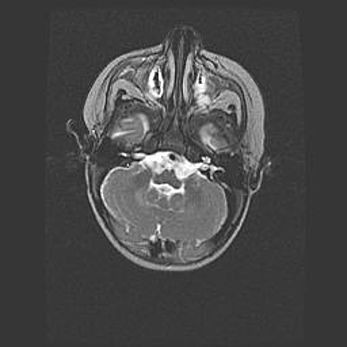

Лейкомаляция с кистозно-глиозной дегенерацией головного мозга.

Возраст: 2 месяца 25 дней

Вес: 6400 г

Окружность головы: 40 см

Срок гестации: 41 неделя

Лейкомаляцию относят к ишемически-гипоксическим повреждениям головного мозга, диагностируемым у новорожденных. При лейкомаляции в головном мозге обнаруживают очаги некроза, возникшие после тяжелой гипоксии и нарушения кровотока. В процессе морфогенеза очаги проходят три стадии: 1) развития некроза, 2) резорбции и 3) формирования глиозного рубца или кисты. Перивентрикулярная лейкомаляция (ПЛ) встречается примерно в 12% случаев среди новорожденных, обычно – у недоношенных детей, причем, частота ее зависит от массы, с которой младенец появился на свет. Наибольшее число малышей страдает лейкомаляцией, если масса при рождении 1500-2500 г.